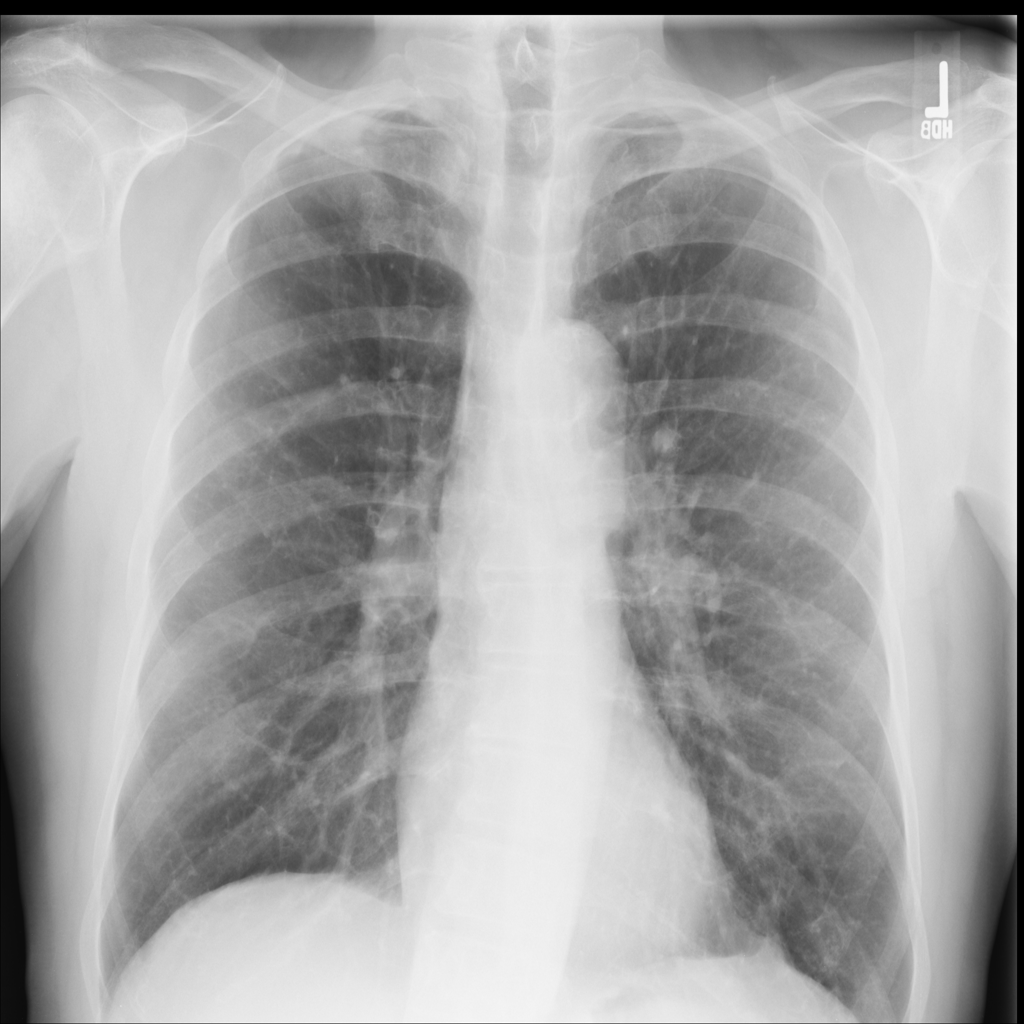

PAT-C255 · IMG-000Emphysema

PAT-C255 · IMG-000

PA